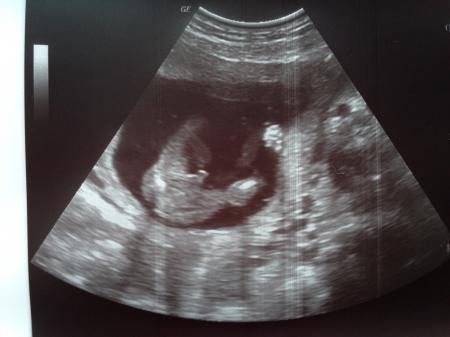

Hallo Mädels, komme gerade von der FÄ wieder. Mit dem Krümel ist alles in Ordnung. Es wurde gezappelt, gewunken und sich gedreht. Alle Werte sind unauffällig. Dann schaute sie nach was es werden könnte und lachte und meinte, dass sei sehr eindeutig: wir verstärken das Team blau Er hat auch gleich alles in stolzer Pracht gezeigt Euch noch einen schönen Tag

Bild zu Outing - Forum für August - Mamis